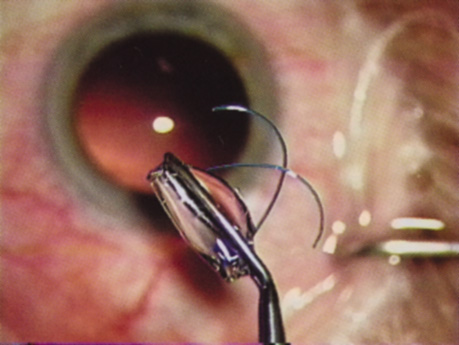

At the turn of the century, the incidence of posterior capsular opacification (PCO), the most common untoward event after surgery, was plummeting as the result of a square edge design on the IOL optic. The haptics themselves had evolved from Prolene material to polymethylmethacrylate and then Alcon introduced a soft haptic on a single-piece acrylic platform. Every company developed an injector for improved IOL insertion, and industry was teaming up with innovative surgeons in developing a number of optic modifications. Attempts to achieve multifocality with diffractive optics had been introduced by 3M and their design team of Richard Lindstrom, John Sheets, and Robert Osher. This technology was placed on the back burner until Allergan developed the array multifocal IOL. Alcon purchased and improved the 3M defractive optic and introduced ReStor IOL on a single-piece acrylic platform. The surgical assault on presbyopia accelerated as Eyeonics developed the Crystalens, the first IOL with a pliable optic aimed at generating accommodation, a concept introduced a decade before by Spencer Thornton.33 A toric optic was developed by Staar Surgical; Pharmacia introduced Tecnis, the first spherical aberration-correcting IOL; and Alcon developed the first blue-light–filtering optic to provide macular protection. The once narrowly defined specialty of cataract and IOL surgery was exploding with new ideas and technologies. Smaller-incision IOLs were being designed that could be injected through <2-mm incisions. A host of surgeons, including Amar Agarwal, Jorge Alio, Richard Packard, Hiroshi Tsuneoka, Virgilio Centurion, Howard Fine, and Randy Olson, were exploring microincisional cataract surgery through 1.5-mm incisions by separating the sleeveless ultrasound tip from the irrigating chopper.

Refractive lens replacement and phakic implantation also were gradually earning a rightful place in anterior segment surgery. In the early 1980s, Franco Verzella from Italy initially removed the clear lens for extreme myopia, but surgeons were concerned about the incidence of retinal detachment in this group of high-risk eyes. Robert Osher performed the first clear lensectomy for hyperopia in 1985 and although the risk of retinal detachment was lower, these eyes were challenging both in surgery and in accurately selecting the IOL.34,35 John Gayton's novel approach of using “piggyback” IOLs met with enthusiasm until interlenticular opacification emerged.36 AcriTec engineers from Germany identified a method of manufacturing lens power up to +60 diopters. Phakic implantation with IOLs fixated in the anterior chamber (Baikoff, Kelman, Choyce) and the posterior chamber (Fyodorov, Adatomed, PRL, Staar Surgical) were being developed. The iris-supported Verisyse (Artisan developed by Jan Worst) became the first phakic IOL approved in the United States.